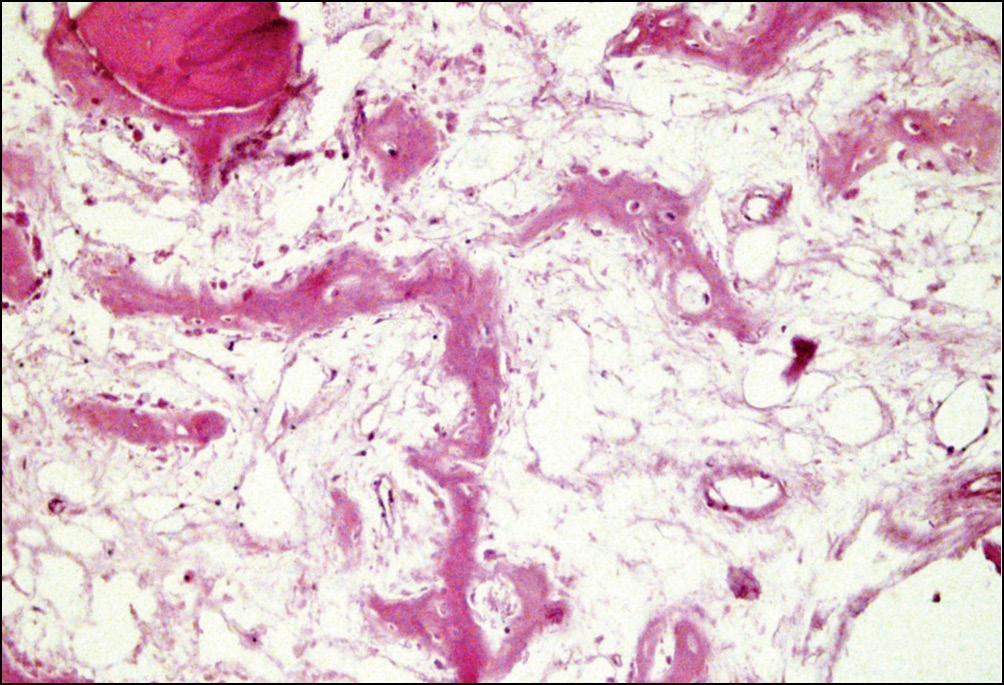

Местами репаративные процессы проявлялись разрастаниями волокнистой фиброзной ткани вокруг осколков костных балок, по-видимому, для последующего использования их как арматурный материал в костеобразовании (рис. 4).

Рис. 4. Репаративные изменения костной ткани в зоне перипротезных переломов бедренного компонента: разрастания волокнистой фиброзной ткани вокруг осколков костных балок. Окраска гематоксилином и эозином. Увел. ×160

Fig. 4. Reparative changes in periprosthetic fractures bone tissue of the femoral component: proliferation of fibrous tissue around the fragments of the bone beams. Staining with hematoxylin and eosin. Magnification × 160